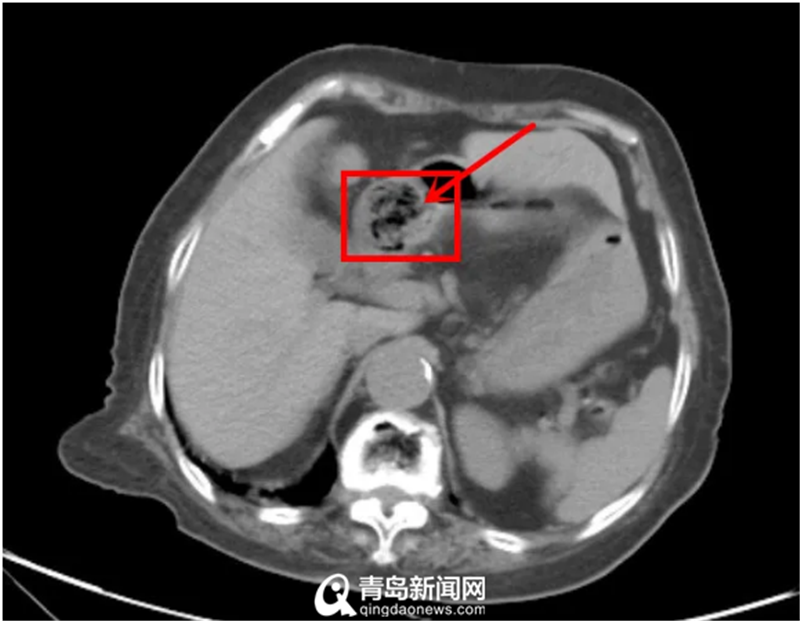

腹部CT可见巨大胃结石

山东大学齐鲁医院(青岛)急诊科接诊后,一边给老人尽快建立静脉通路进行输液维持生命指征,一边迅速给老人复查了腹部CT,结果显示胃结石仍在,堵在了幽门前方造成梗阻症状。为寻求进一步治疗,老人住到了消化内科。这时,距离老人出现症状已经过了一个多月,由于长期进食差,她的身体十分虚弱。

经过初步检查,一方面,由于发病时间较长,结石已经变得极为坚硬,碎石难度加大;另一方面,经仔细分析CT影像,发现结石大部分已经越过幽门,随时有整体掉入十二指肠的风险,需要尽快碎石。